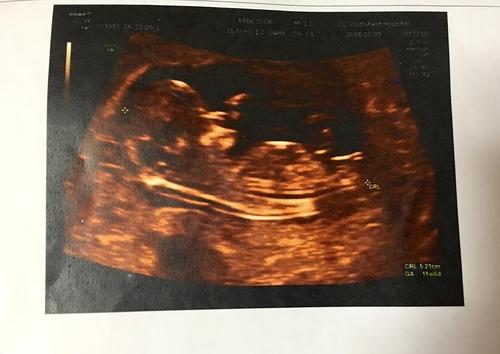

目前,四維彩超可以說是診斷胎兒發育情況最有效地手段之一,因為它拍的非常清晰,能夠多角度多方位觀察寶寶的發育狀況,通過拍彩超,醫生可以認定胎兒是否畸形,并幫助孕媽咪提前做出相關的措施。

四維彩色超聲簡稱彩超,是非常先進的孕檢手段。四維超聲孕檢手段是運用3D超聲圖像以及時間維度參數,顯示出胎兒當下的動態活動圖像。那么彩超是否有輻射?四維彩超是否會給胎兒發育造成不利影響?

與傳統B超相比,四維彩超的畫面比普通B超要清晰很多,而且能夠立體直觀地展現出胎兒的一舉一動。四維彩超能有效判定胎兒是否畸形,在很大意義上幫助孕媽咪降低畸形兒的出生概率。

用四維彩超進行孕檢,是能夠多方位、多角度地對胎兒的狀況進行觀察。醫生能夠根據彩超的結果,來檢查胎兒是否能夠健康生長發育。